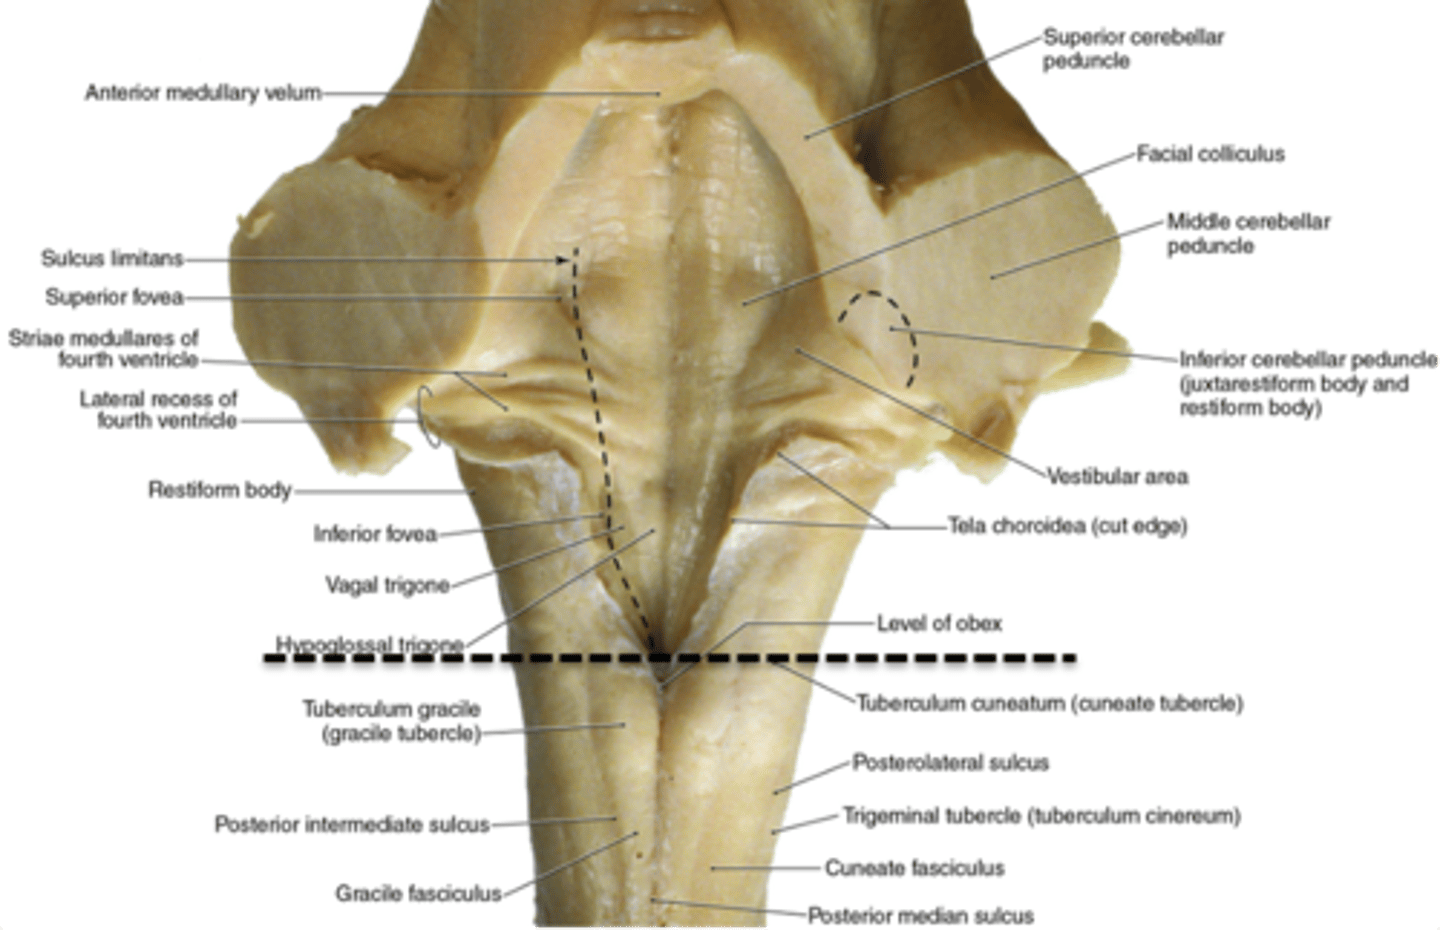

what are the 2 tubercles found on the closed (caudal) medulla?

1. gracile tubercles (more medial, touch/proprioception from lower body)

2. cuneate tubercles (more lateral, touch/proprioception from upper body)